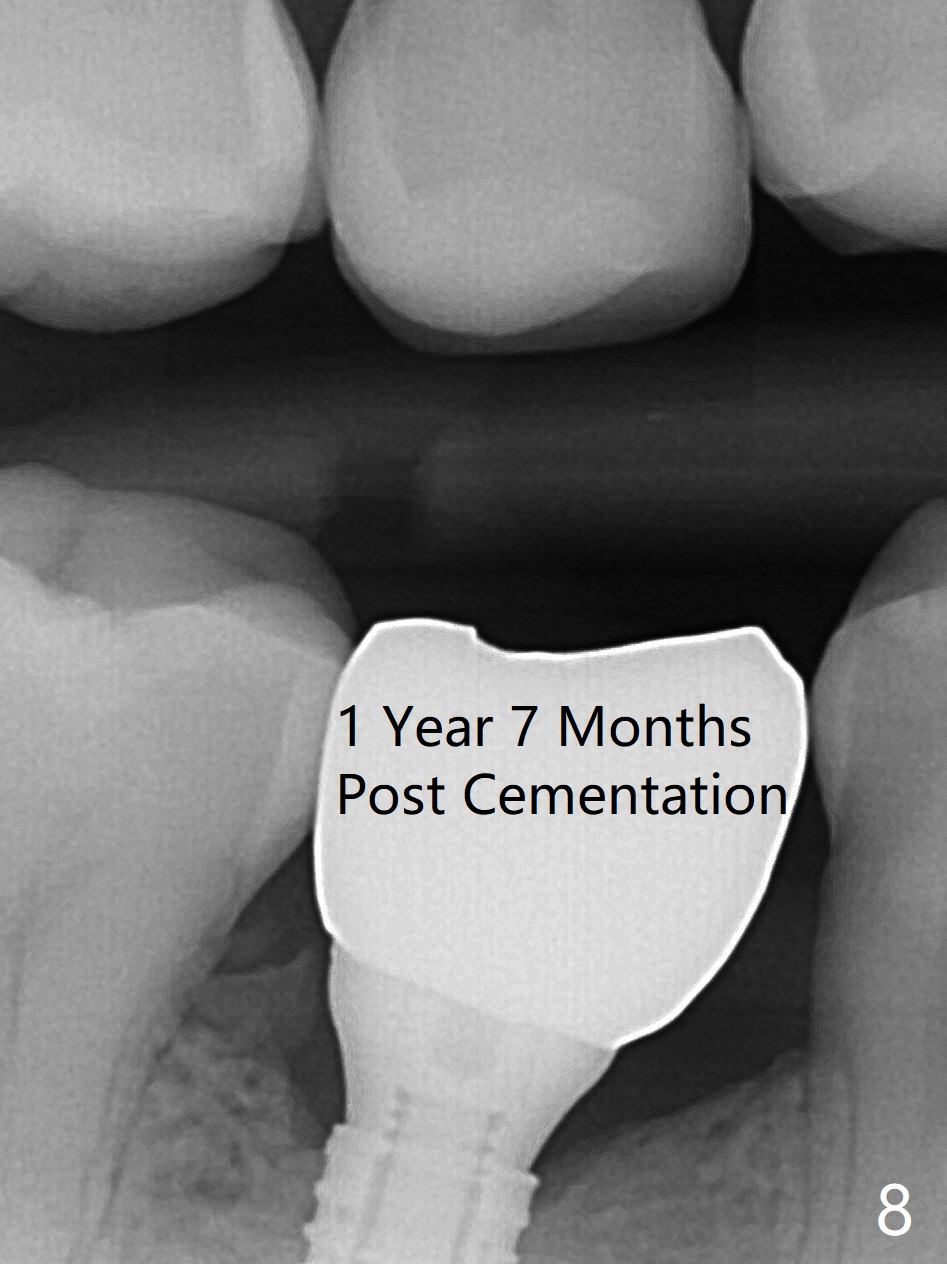

The base of the edentulous ridge at #29 looks wide (Fig.1), but the most coronal portion is the thin soft tissue (Fig.2). It appears that there has been bone resorption since extraction. The initial osteotomy depth is 11.5 mm (Fig.3). Since the Mental Loop seems to be nearby, the depth of subsequent osteotomy (3 mm) remains the same (Fig.4). Although the final depth of osteotomy is 13 mm, the implant placed is short (3.8x11.5 mm, Fig.5,6), as compared to the immediate implant (3.8x18 mm) at the contralateral side (#20). There is mild bone resorption mesially 4 months postop (Fig.7). The crown is loose (poor osteotomy position, guide necessity) 7 months post cementation immediately prior to 18 cementation, although there is no gross bone losss 1 year 7 months post cementation (Fig.8).